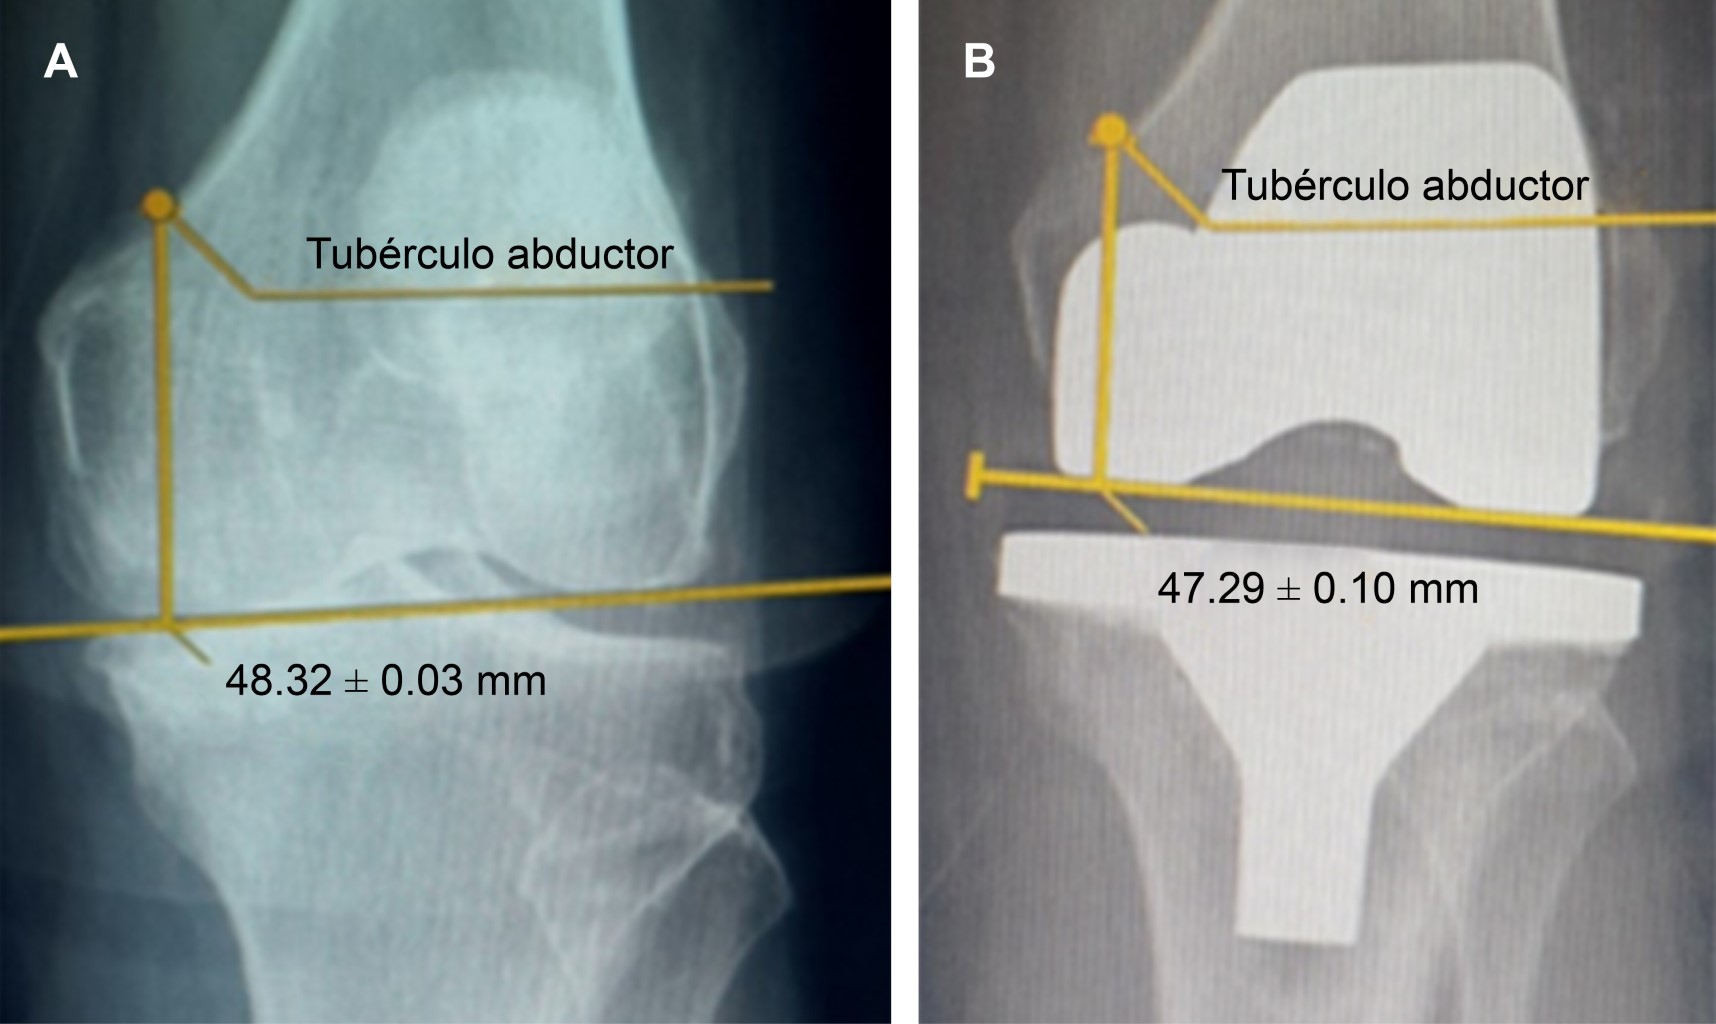

Association between post-surgical anterior pain and inadequate reproduction of the post-surgical joint line in primary knee arthroplasty

Introduction: Reproduction of the articular line is one of the most important indexes to determine the satisfactory results of prosthetic knee surgery but there are few studies focused on the review of these cases in a medium term and less, in the development of chronic pain. Material and methods: Retrospective, longitudinal and observational study; which includes patients with a total primary knee arthroplasty in a period of 2017 to 2019 and whom will have a follow-up of a post-surgical year. Results: Of the 32 cases after one year of evaluation only 14 (44%) cases reported the presence of chronic pain. The analysis of the association between pain and the presence of displacement or restoration in the joint line showed to be significant (p = 0.0001), with Fisher's exact test. Conclusions: Although the articular line is an important factor in determining the flexion, extension and range of movement, we conclude that the no restoration of the articular line is related to the development of the anterior post-surgical pain in a long term.

Figure 1